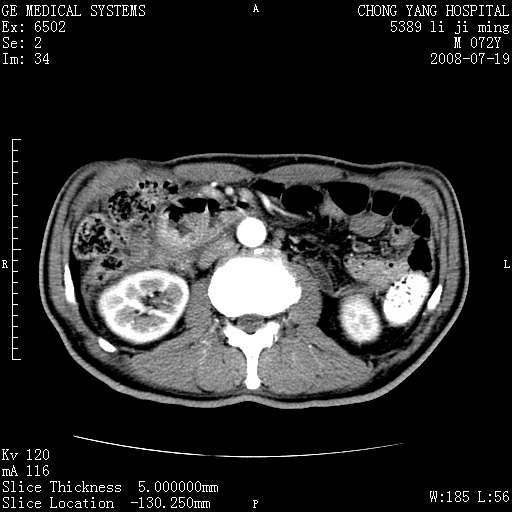

以下是引用zjzjr在2008-7-19 20:57:00的发言:[br]胰头增大,边缘模糊,周围可见渗出影,右侧肾前筋膜增厚.支持胰腺炎.

以下是引用yangyudong333在2008-7-20 6:56:00的发言:[br]胰腺增大尤以胰头明显,边缘模糊,周围可见渗出影,右侧肾前筋膜增厚,肠管於涨.支持胰腺炎

以下是引用不学无术在2008-7-19 23:15:00的发言:[br]胰腺增大尤以胰头明显,边缘模糊,周围可见渗出影,右侧肾前筋膜增厚,肠管於涨.支持胰腺炎